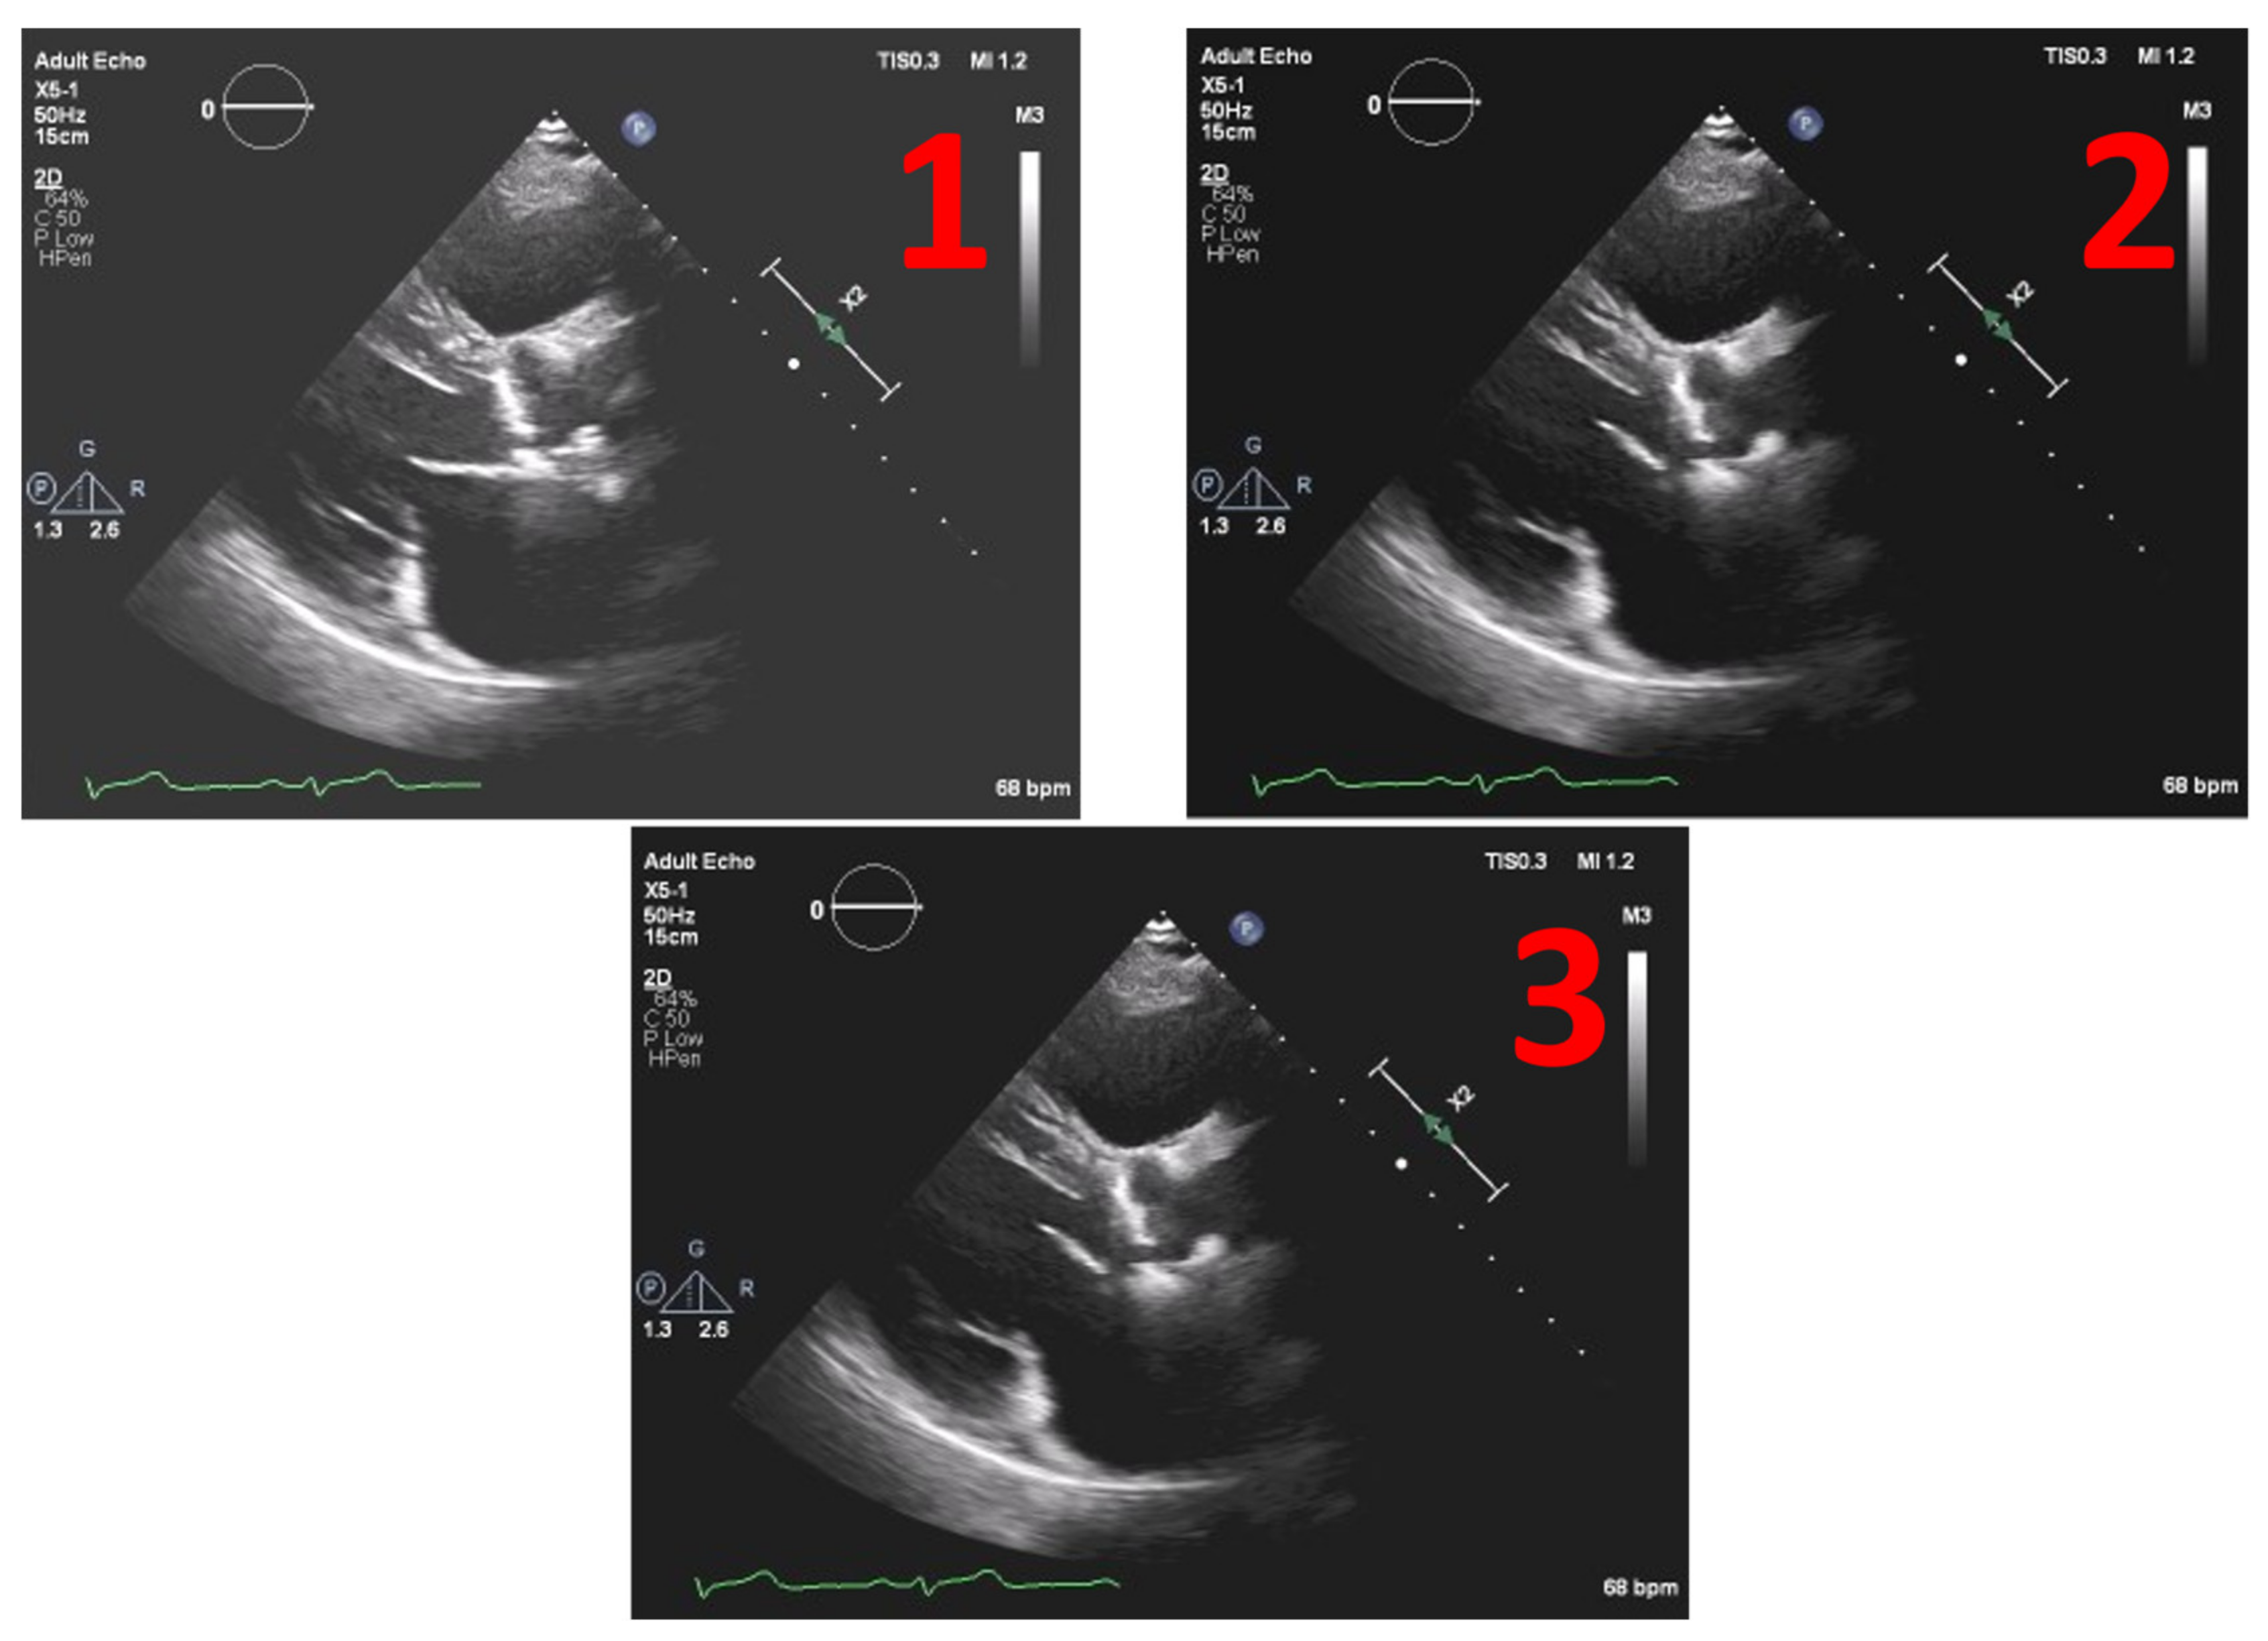

This method was tested on several images. Figure 8 depicts the example of one echocardiography with the most used different types of gains set in a post-processing stage, with the settings Window Width fixed at 250 and Window Level (WL) permuting between 75, 100 and 125.

In Figure 9 we have the normalized result of the calcium threshold obtained with these representative echocardiography cases, showing coherent results, extracted from the calcium present in the aortic valve, where we have the mean and the median of the values extracted from our ROI, the scale being from 0 to 255 (the greyscale pixel values). We can see that the values of pixels intensity extracted have a low absolute variation, suggesting the validity of our model since we have the same image with different gains.

Figure 8. Echocardiography examples with different Windrow Levels (WL) and fixed Window Width of 250 (1) WL = 75, (2) WL = 100, and finally, (3) WL = 125.

Figure 9. Threshold values of pixel intensity for calcium, extracted from echocardiographic images with different post-processing gains. Windrow Levels (WL): (1) WL = 75, (2) WL = 100, and finally, (3) WL = 125, all with a fixed Window Width of 250.